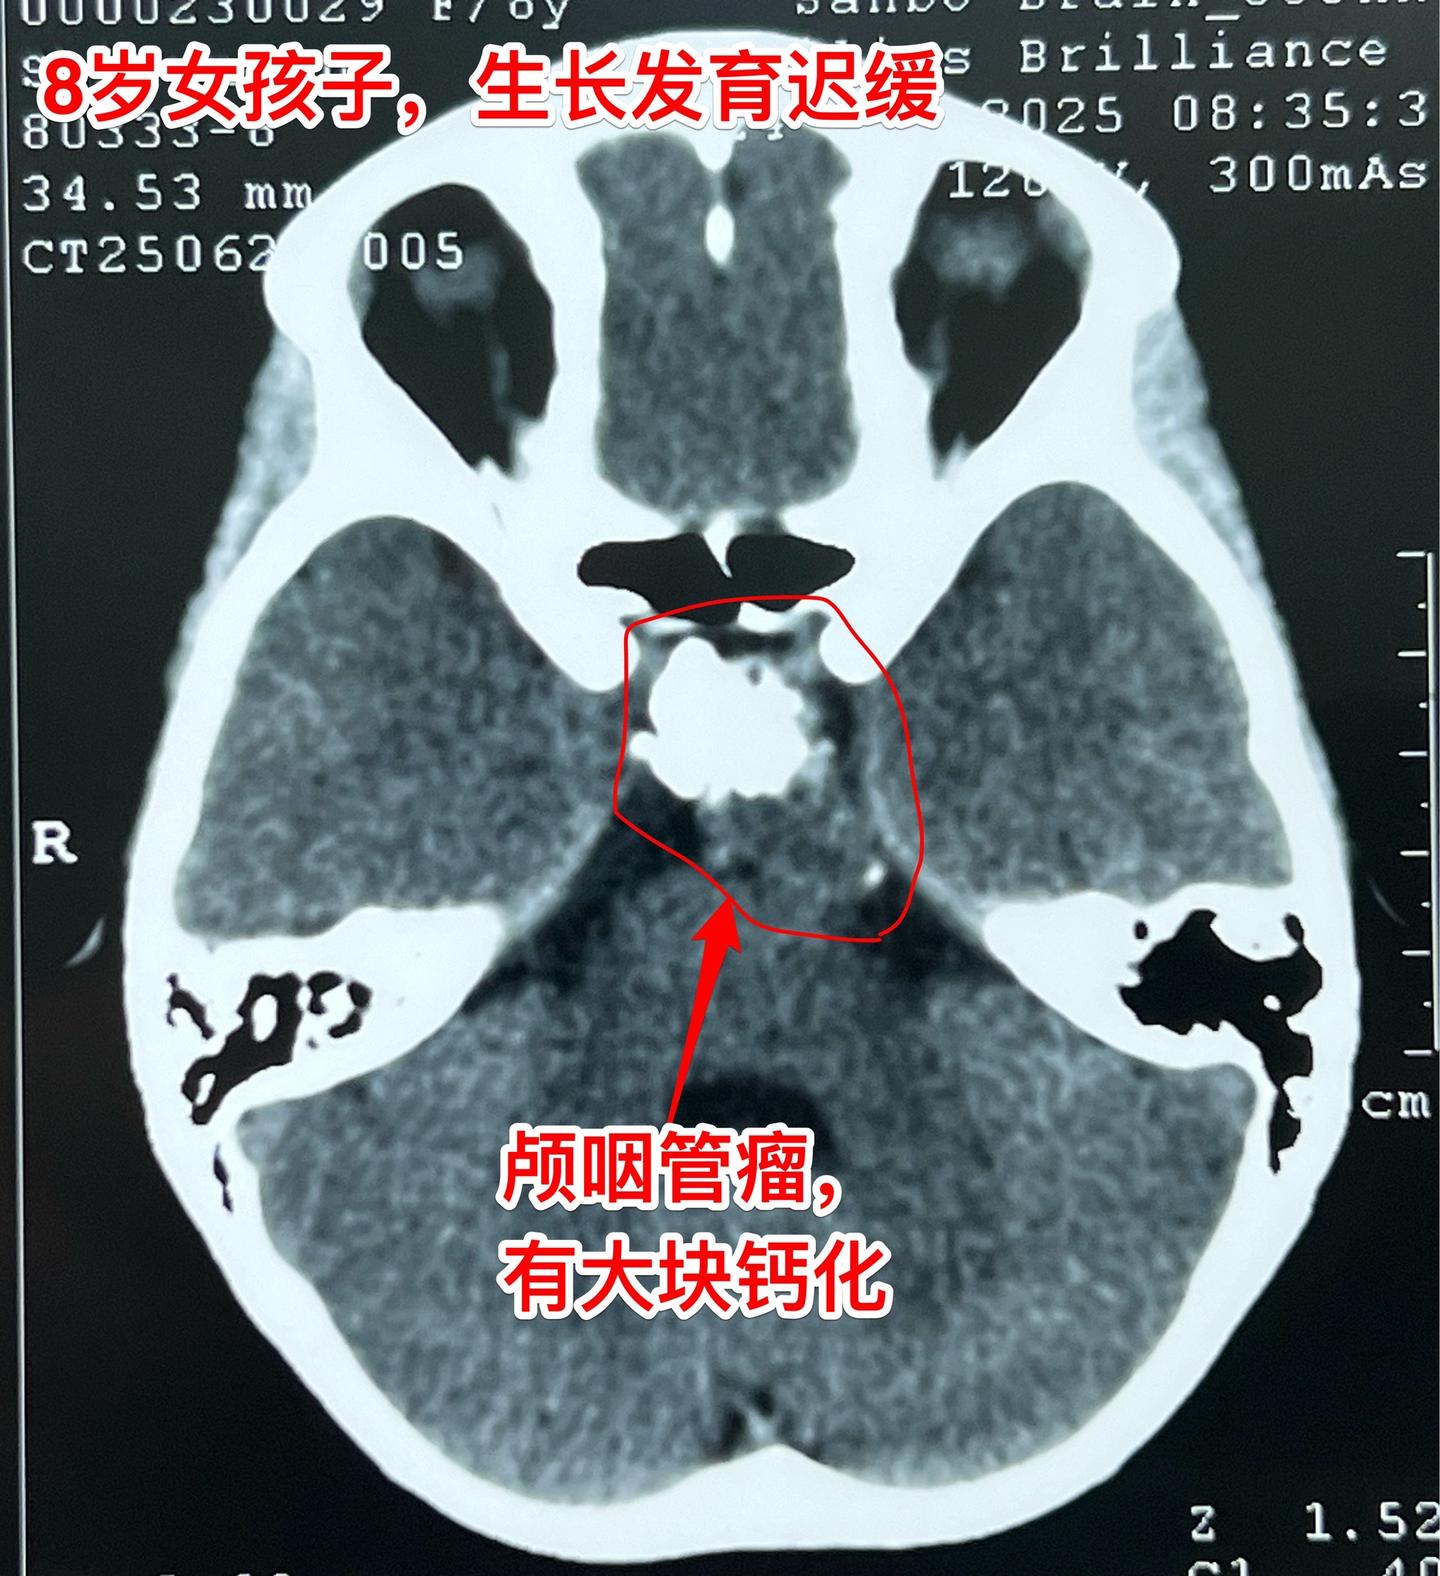

八岁烟台女孩子身高增长缓慢—原因找到了。八岁女孩子,父母都是大高个。近两年女孩子身高增长很缓慢,一开始没有引起重视。随着身高差距拉大,家长重视起来了。 2025年6月到医院检查头部磁共振、CT,一下子就找到原因了:脑部长了颅咽管瘤,这个颅咽管瘤还有一大块钙化。 女孩子除了身高增长缓慢之外,无视力下降,无多饮多尿症状,精神状态也很好。 女孩子的舅舅也是神经外科医生,上周找我看了门诊,他们接受开颅手术。 今天的手术很顺利,颅咽管瘤得到完全切除。